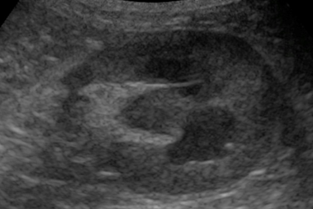

L'insuffisance rénale reste une cause majeure de morbidité et de mortalité chez les carnivores domestiques. Il est fondamental de poursuivre sa démarche au-delà de la mise en évidence de l'azotémie, afin de proposer une meilleure prise en charge.

Nous aurons le plaisir d’accueillir pendant cette journée le Pr Christelle MAUREY-GUENEC et sa résidente pour nous illustrer, au travers de cas cliniques, les actualités sur la prise en charge de la maladie rénale chronique, mais aussi des approches thérapeutiques spécifiques adaptées à la cause de l'insuffisance rénale, qu’elle soit aiguë ou chronique.

- mener une conduite diagnostique pour identifier les causes d'une azotémie et les complications d'une insuffisance rénale ;

- de proposer un traitement adapté à l'origine de l'azotémie.